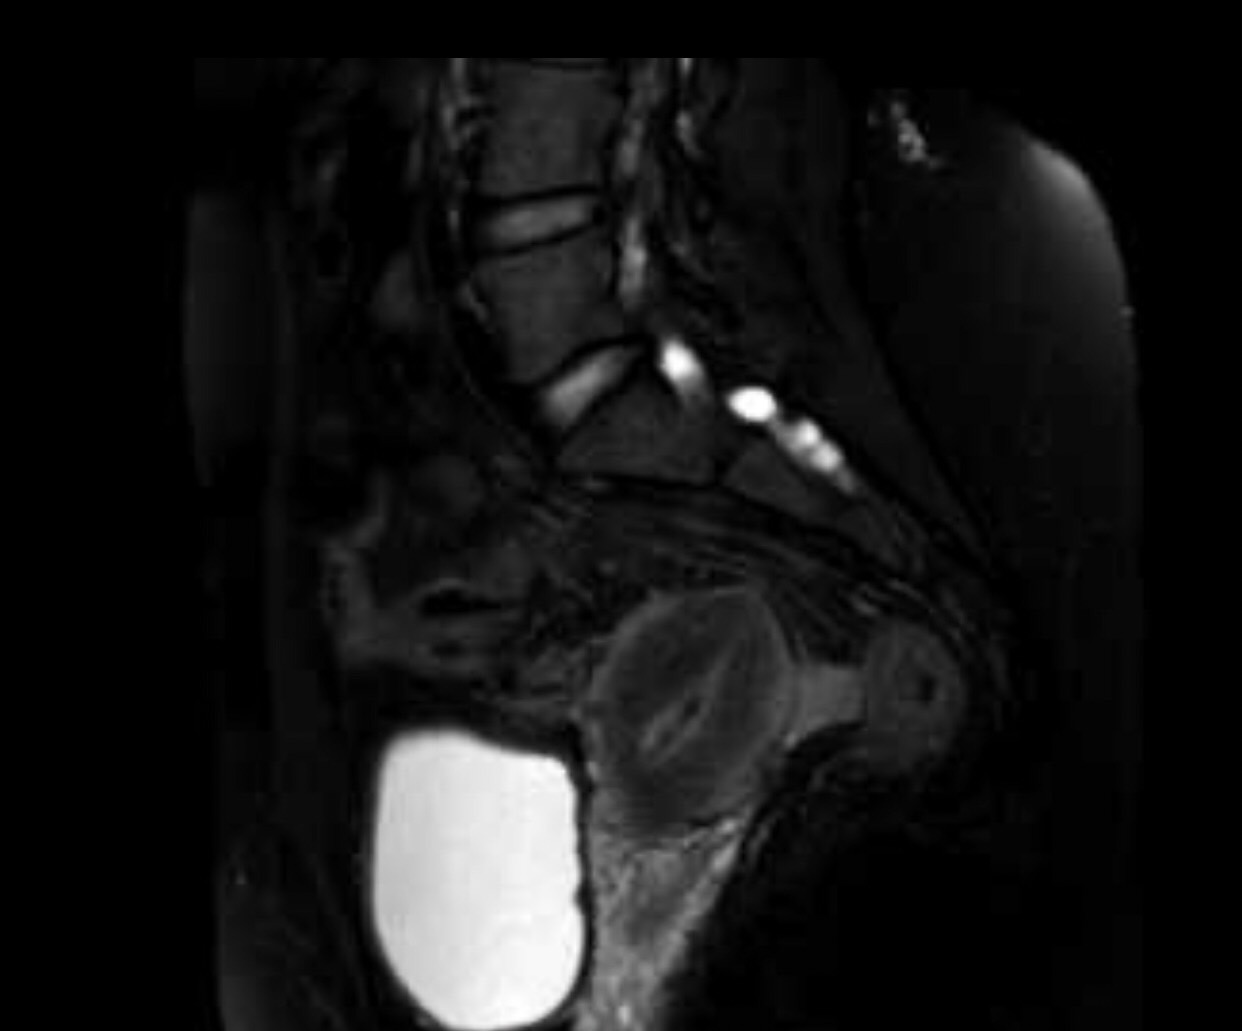

มีใครช่วยดูภาพ MRI Pelvis ของเราได้ไหมค่ะ

เรามีอาการทางประสาท ปวดแสบปวดร้อนที่กล้ามเนื้อขาอ่อน ชาขาลงเท้าเป็นบางครั้ง ส่วนมาจะเจ็บๆคันเหมือนโดนมดแดงไฟกัด บริเวณขาอ่อนด้านใน บางทีก๋กล้ามเนื้อสะโพกกับขาหนีบล็อกหกเกร็ง สะโพกรู้สึกหกเกร็งขาดความยืดหยุ่นเหมือนหนังยางที่ยึดแล้วมันปริแตกเป็นริ้ว เพราะหมดสภาพ บางทีก็แสบบริเวณกล้ามเนื้อเหนือหัวเข่า เรากำลังตามหาผู้ใจบุณช่วยวิเคราะห์ผล MRI ให้เราได้หลังไมค์มาเลนค่ะ เรายินดีส่งไฟล์ที่เป็น Full Version ให้ทางไลน์

จากรูปจุดขาวๆก้อนเล็กคืออะไรค่ะ